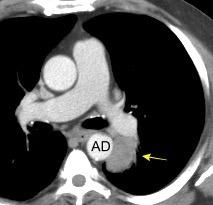

85. ENSANCHAMIENTO MEDIASTÍNICO AGUDO

Hematoma intramural

Disección aórtica

Rotura de aneurisma aórtico

Mediastinitis aguda